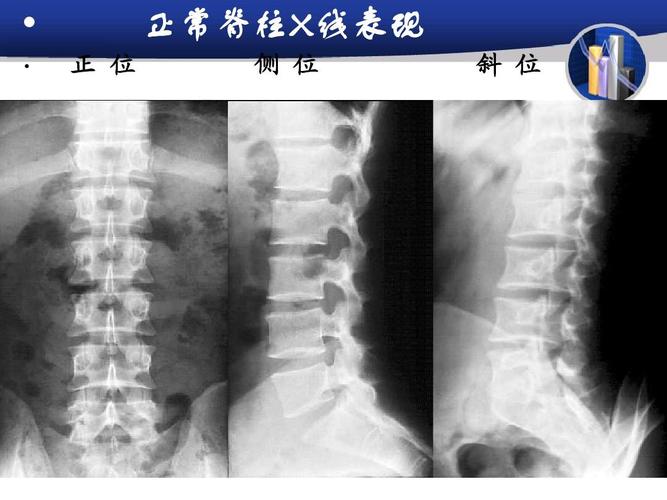

研究生医学影像学-骨与软组织ppt